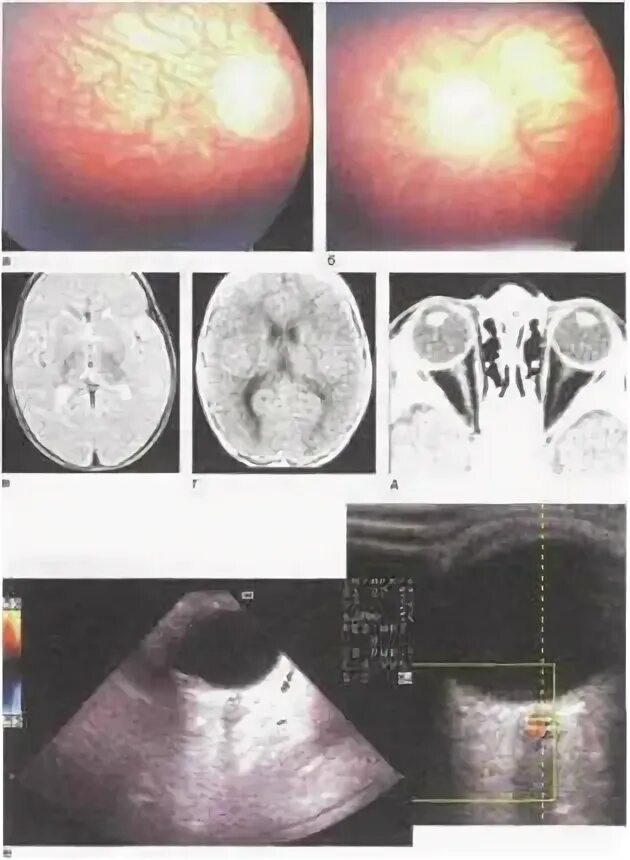

Лечение аплазии